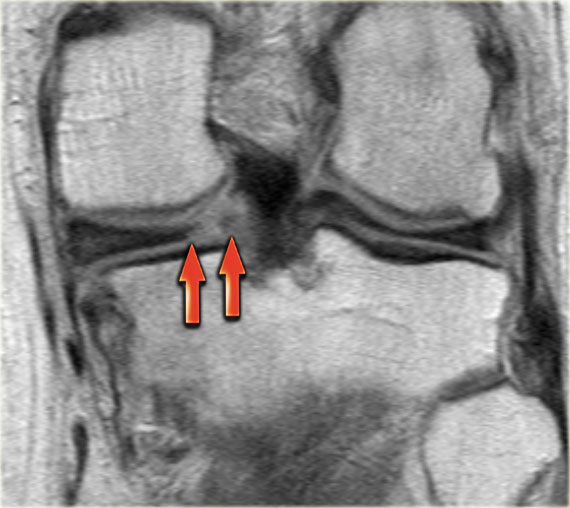

Cùng ca bệnh trên với hình ảnh mặt phẳng sagittal.

Lưu ý phần bị rách của sụn chêm chạy ra phía trước qua hố gian lồi cầu (các mũi tên)

- Thông thường chỉ có hai cấu trúc chạy trong hố gian lồi cầu. Ở đây chúng ta thấy dây chằng chéo sau bình thường.

- Dây chằng chéo trước bình thường.

- Phần bị rách của sừng sau như là ‘cấu trúc thứ ba’

trong hố gian lồi cầu. - Phần bị rách chạy ra phía trước.

- Phần bị rách nhập vào sừng trước và giả tạo hình ảnh rách dọc ở sừng trước.

Lưu ý phần còn lại nhỏ của sừng sau.